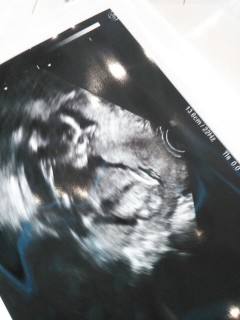

横顔と身体☆

先生が「これが顔ですね~」と言うと、聞こえているのか、サッと隠して…先生と笑っていました。

その後は、お腹の中で足を伸ばしてくつろいで、頭をぽりぽり掻いていました(笑)

正面をうつしたとき、手を振っていました。AC=9.67cm